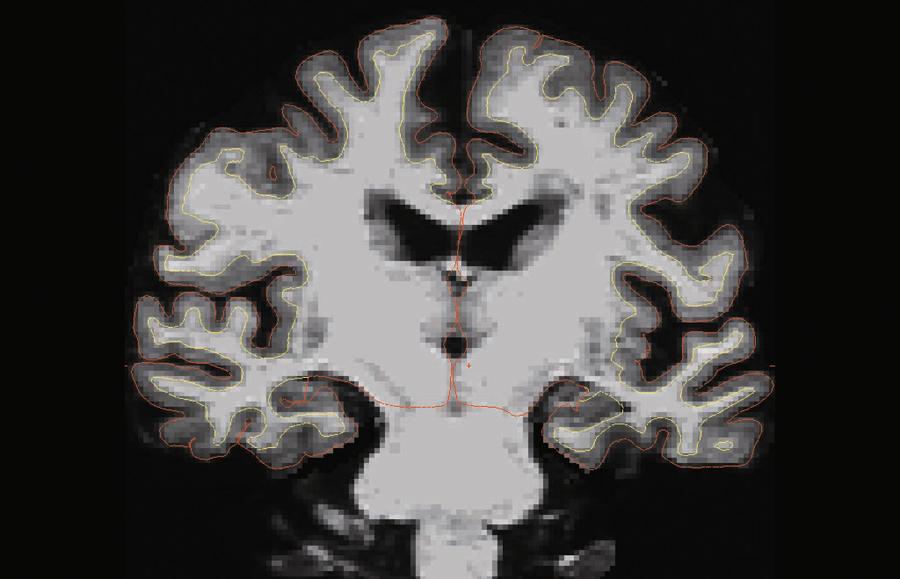

Badacze próbujący rozwikłać zagadkę długowieczności kierują swoją uwagę na ludzi, którym z jakichś powodów udało się oszukać czas. Należą do nich m.in. superagersi, czyli osoby w wieku 80 plus, których pamięć działa tak samo sprawnie jak u pięćdziesięcio- czy sześćdziesięciolatków. W dobie drastycznego starzenia się społeczeństwa i zwiększonej zapadalności na choroby neurodegeneracyjne odkrycie mechanizmów pozwalających na ochronę pamięci jest dziś na wagę złota. Do tej pory wykazano, że superagersi mają nieco inną niż typowi seniorzy budowę mózgu oraz tworzą wyjątkowo silne relacje społeczne. Badania wykonane w skanerze MRI ujawniły u nich większą ilość istoty szarej w obszarach mózgu odpowiadających za pamięć i ruch. Jak się później okazało, mogą pochwalić się lepszymi funkcjami motorycznymi, zwinnością i równowagą, choć poziom aktywności fizycznej nie odbiega w ich przypadku od zwyczajnego seniora. Nie bez znaczenia pozostaje też styl życia superagersów sprzed kilkudziesięciu lat. W wieku średnim regularnie ćwiczyli, dbali o higienę snu i wykazywali się niezależnością. Większość z nich doskonaliła też swoje umiejętności muzyczne, zarówno amatorsko, jak i profesjonalnie. Co ważne, cieszyli się dobrym zdrowiem psychicznym, rzadziej bowiem występowały u nich depresja czy stany lękowe.

Skan MRI mózgu superagersa. Grubość kory mózgowej (szary) zmniejsza się dwukrotnie wolniej niż u typowego seniora.Northwestern UniversitySkan MRI mózgu superagersa. Grubość kory mózgowej (szary) zmniejsza się dwukrotnie wolniej niż u typowego seniora.